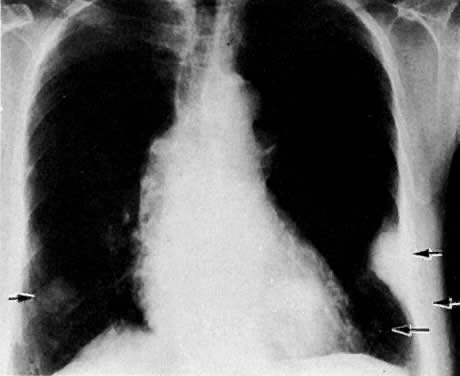

Metastatic spread to the chest from gynecologic malignancies is uncommon and occurs predominantly by the hematogenous route. Lymphatic spread is rare.133,134,135 At autopsy, metastatic pulmonary lesions were found in 27.9% of patients with cervical carcinoma,117 30.2% with endometrial carcinoma,117 and 37.2% with ovarian carcinoma (see Table 4).118 In pretreatment chest radiographs, however, the incidence of chest metastases was found to be less than 1% in two separate studies.108,136 Ovarian carcinoma can spread via the peritoneal cavity through the diaphragm into the pleural cavity, causing malignant pleural deposits and effusions.

Radiologic Examinations and Findings

The posteroanterior and lateral chest radiographic examination is a standard procedure in staging gynecologic malignancies. Decubitus views are performed to confirm the presence of free pleural effusion. The side with the suspected effusion is placed in the dependent position; if free fluid is present, it will layer along the lateral chest wall.

Chest CT is a more sensitive and accurate test that can be used to confirm the presence of lesions and to differentiate benign from malignant ones. CT better visualizes lesions in the apices of the lungs, costophrenic sinuses, cardiophrenic angles, mediastinum, and supradiaphragmatic areas. In some cases, pleural-based lesions (Fig. 53) and loss of rib detail are also better demonstrated by CT.137 CT can identify diffuse calcification by assigning a higher number to the nodule. Unfortunately, CT cannot differentiate benign from malignant nodules when they are not calcified. Recent advances in CT technology, including spiral CT, have been used to reconstruct three-dimensional images of the chest and detect tumor spread to the pleura. In addition, spiral CT probably has a higher rate of detection of metastatic nodules than conventional CT, because of the lack of respiratory motion artifacts. CT-guided fine-needle percutaneous aspiration biopsy is used to differentiate benign from malignant chest nodules with a high degree of accuracy.

Fig. 53. A. Posteroanterior chest film with metastatic lesion in left upper lung field, second anterior interspace ( arrow ). B. Axial CT scan shows the lesion ( arrow) projecting from the pleura.